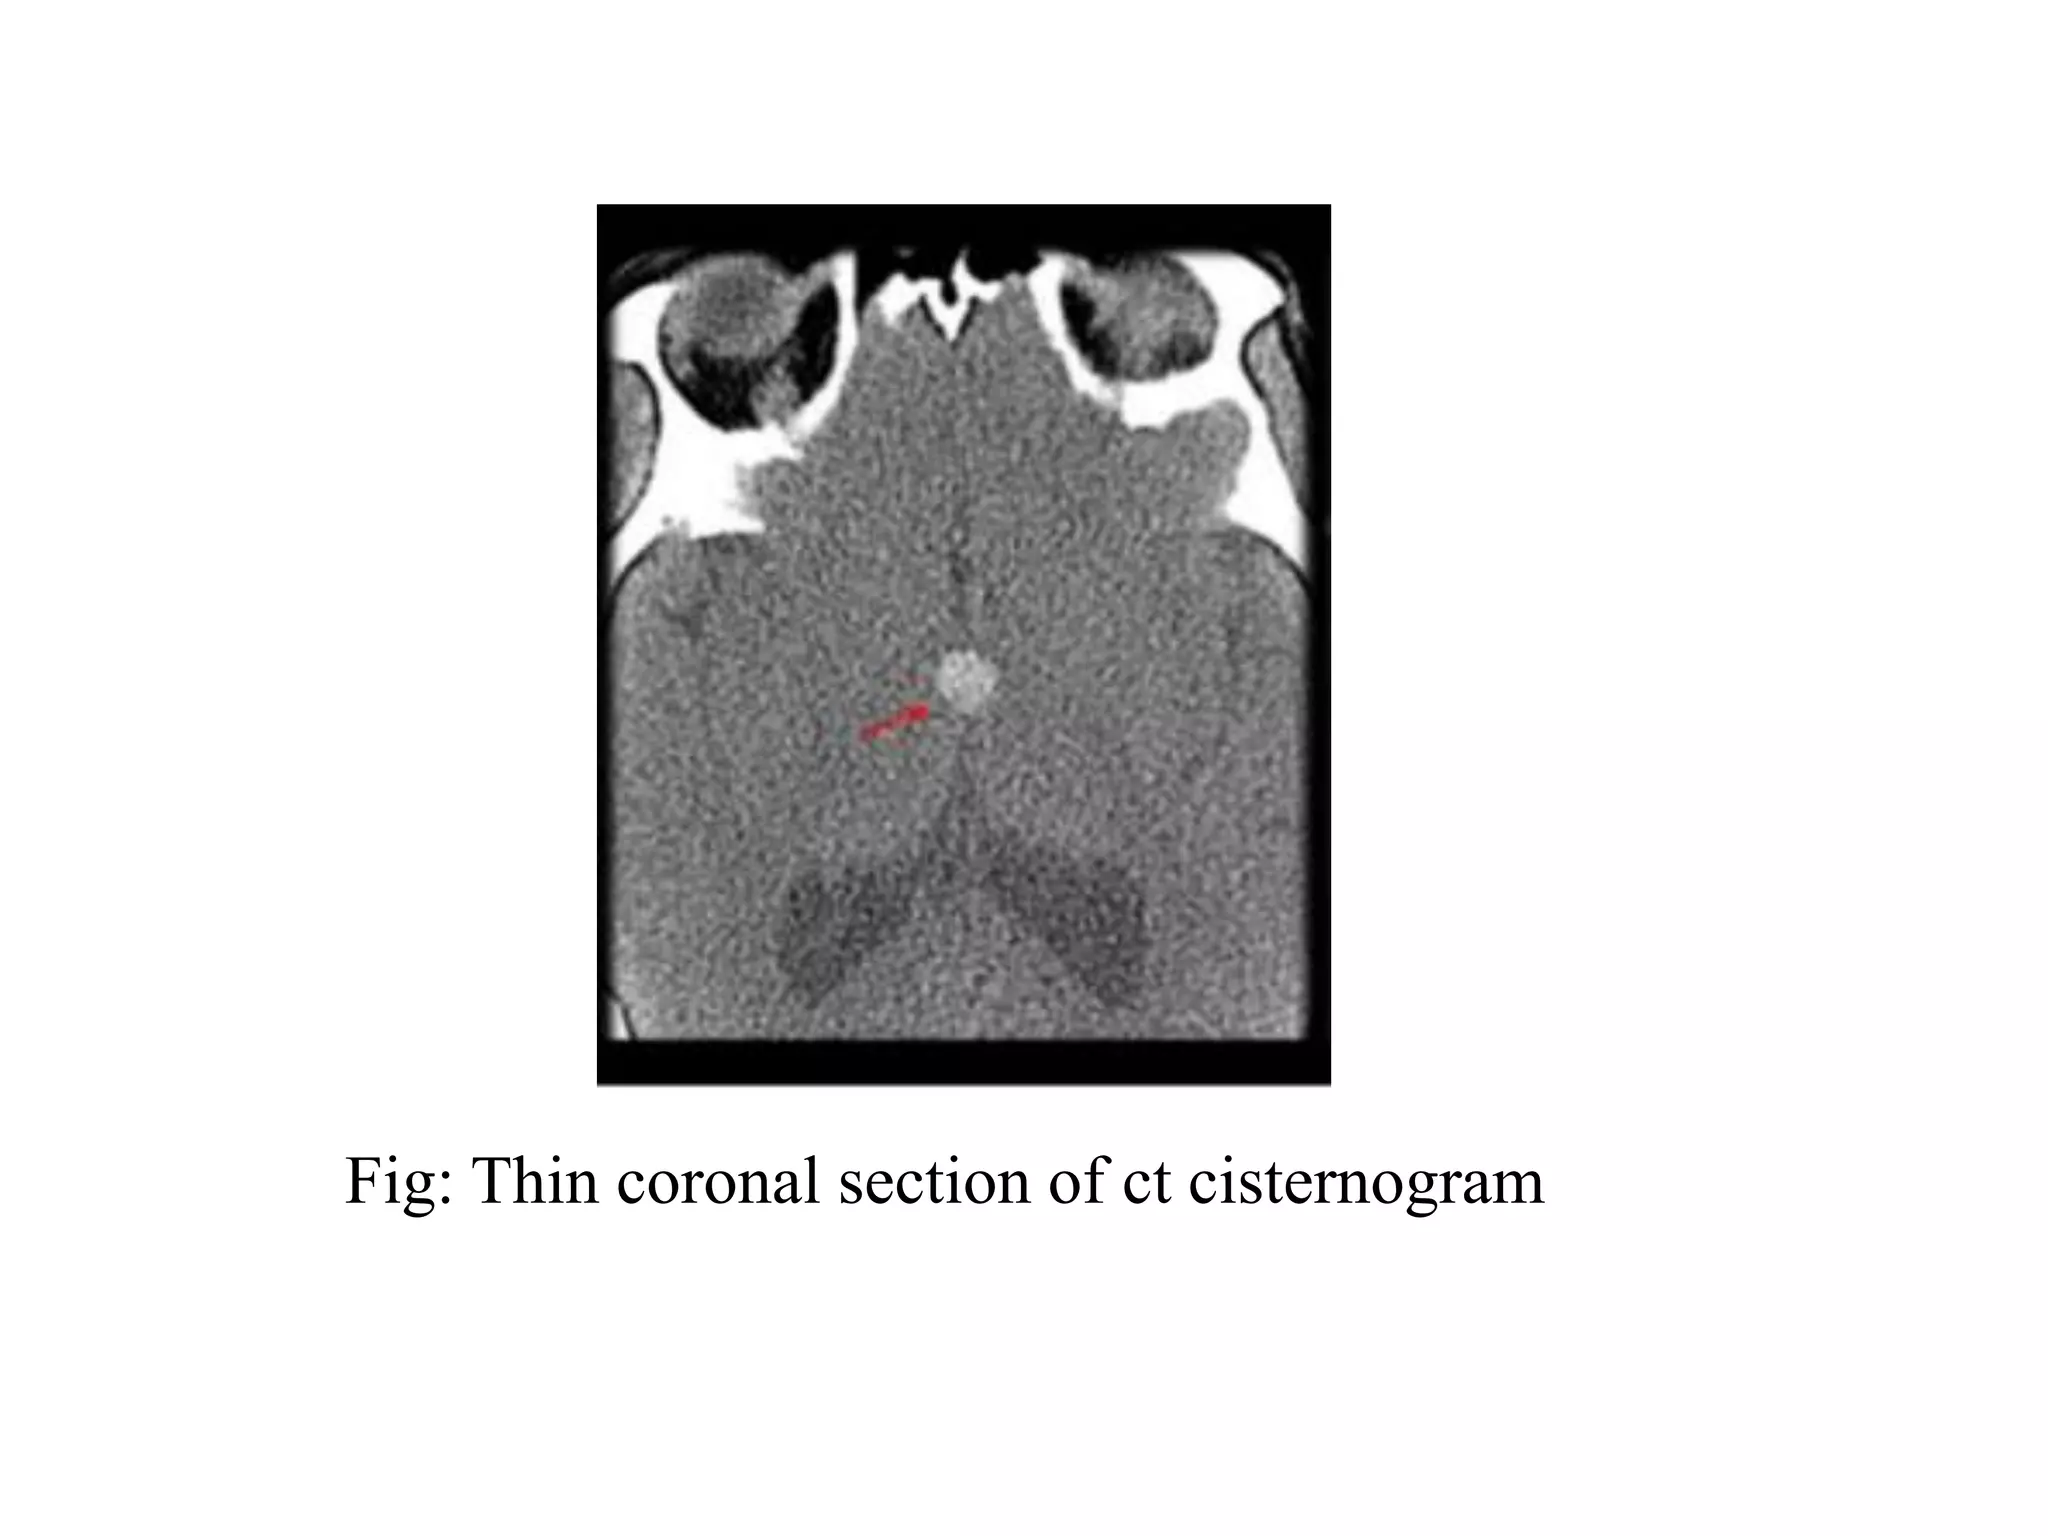

Fig: Thin coronal section of ct cisternogram

Fig Thin coronal section of ct cisternogram

Criteria of image quality

• Symmetric position with the orbital plates

overlapping with each other.

• Absence of the motion artifacts.

• Absence of beam hardening.

• Optimal opacification of the cisterns and the

sulcal spaces.